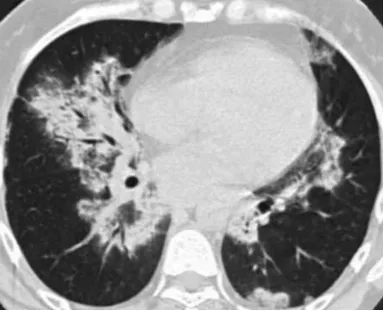

治疗前

治疗1月后